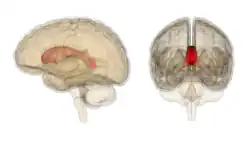

Sagittal section of a brain, front part to the left. The corpus callosum can be seen in the center, in light gray